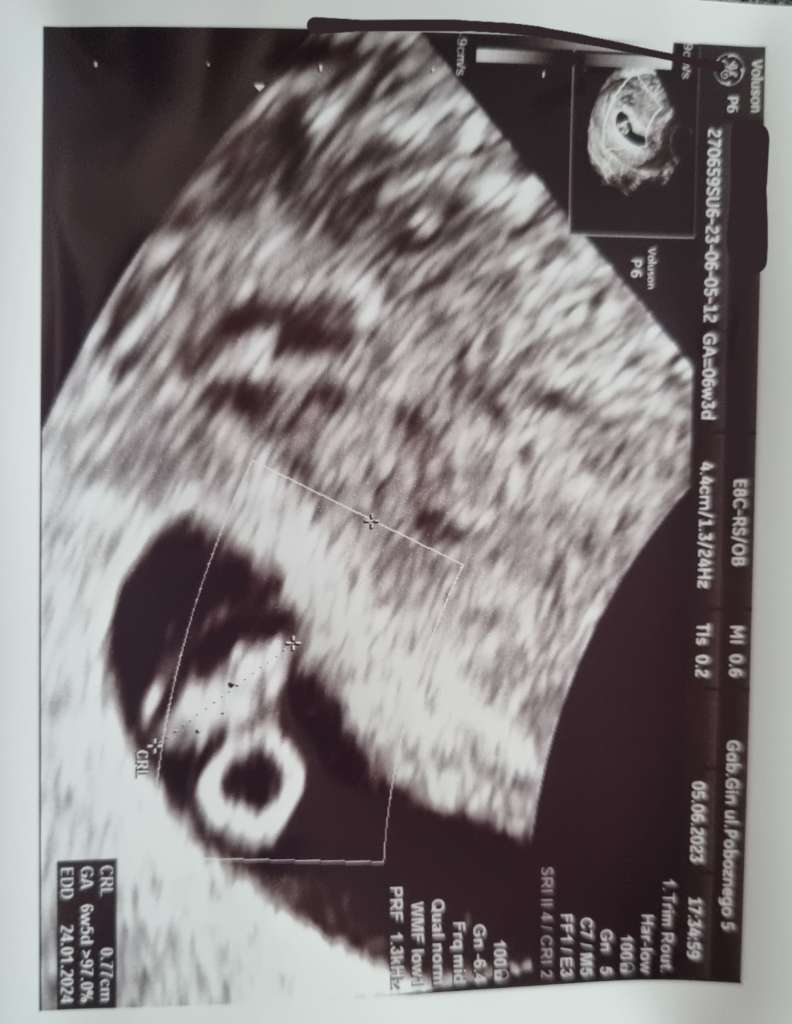

Dzień dobry 🫢❤️ bije mi serce, wg @ 6+5, według usg 7+1, termin 23.01 lub 26.01 😂🫢🥰❤️

Załączniki

• 904d1f58-2557-457d-b677-3e10d58b7537.jpeg

904d1f58-2557-457d-b677-3e10d58b7537.jpeg

60,1 KB · Wyświetleń: 140